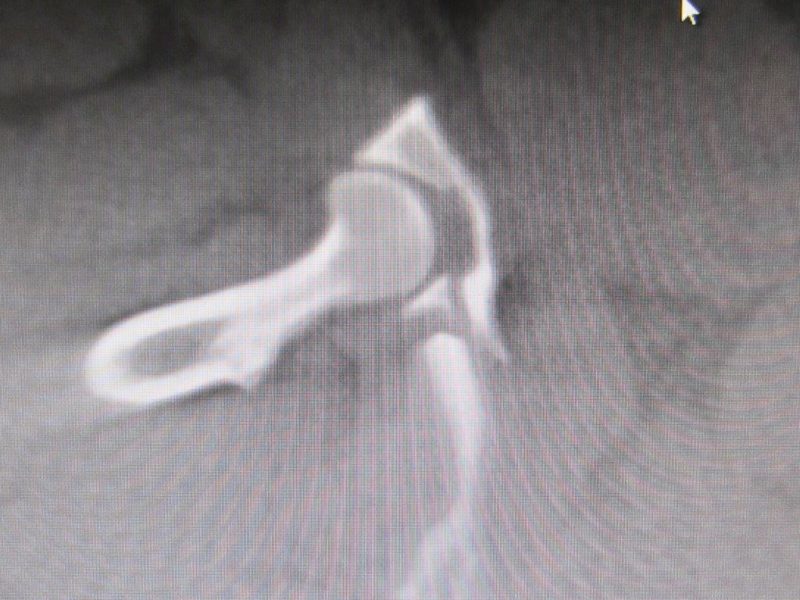

Auf der Abbildung (Bild 4 mit Pfeil) lässt sich eine Fraktur (Bruch) des Kreuzbeins mit einer geringgradigen Verschiebung darstellen. Diese verläuft in der Längsachse des Knochens und tangiert nur ganz gering den Rückenmarkskanal, in dem das Rückenmark und die Nerven verlaufen. Zusammen mit den Besitzern entschlossen wir uns, vorerst auf eine Operation zu verzichten und das Tier nur in einer Box ruhig zu halten, sowie die notwendigen Medikamente zu geben. Es sollte genauestens darauf geachtet werden, daß die normalen Körperfunktionen mit Urin- und Kotabsatz funktionierten und keine nervalen Ausfälle aufträten.